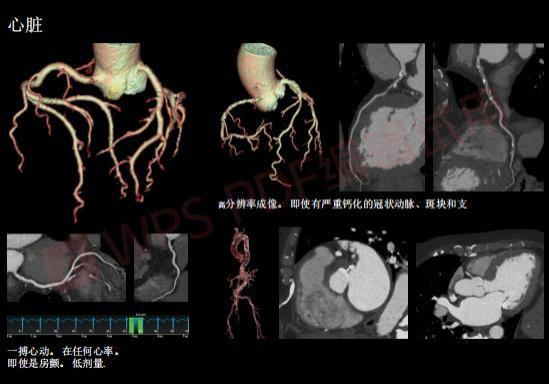

低剂量扫描心脏

在CT增强扫描时,尤其是CT血管造影(CTA)成像时,利用低千伏(KV)扫描,血管和增强组织的信号有很大的提升,使血管的显示更加锐利,肿瘤的边界更加清晰,无论是对于医生基于图像进行疾病的判别,还是从图像中提取血管的狭窄程度、肿瘤的体积等定量化信息,都有很大的帮助。但以往的绝大部分CT设备中,低千伏(KV)扫描只能应用于体型瘦小的患者或者儿童。如果患者的体型稍胖,低千伏(KV)扫描时的图像噪声就会非常大,将不得不采用高千伏(KV)进行扫描。在Revolution Apex CT上,任何体型的患者都可以使用低千伏(KV)的扫描条件,而不用担心图像噪声。这使得不同体型患者间可采用一致的数据采集标准,提高了信号强度和数据准确性。对患者而言,可实现更低射线剂量的精准诊断,减少漏诊的可能性,让每一次扫描都能获得以往CT设备无法比拟的高清图像质量。

对于一些肾功能不好的患者,打造影剂可能会有风险,但基于Revolution Apex CT的图像处理技术,现在只要注射原来的三分之一到一半的剂量就可以清晰成像。Revolution Apex CT安全性更高,剂量更低,可降低82%辐射剂量、50%造影剂用量。更低的辐射剂量,更低的造影剂用量,为患者带来了更安全的CT检查。与此同时,Revolution Apex CT的舒适性更强,采用的是80cm超大机架孔径,最大限度地降低了局促空间给患者带来的不适,消除患者紧张情绪,让他们在自然的状态中轻松完成检查。